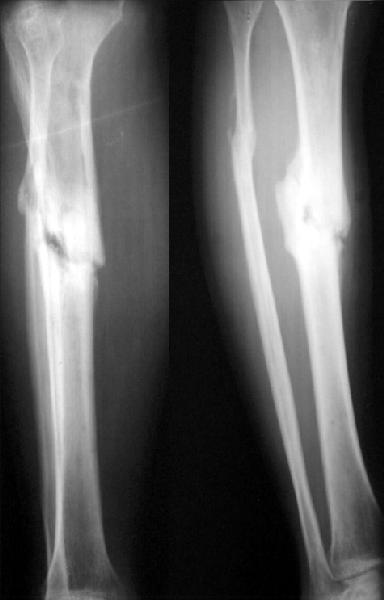

I agree. The non-union looks like a 'stiff hypertrophix non-union'. So, leave the nail in-situ. Remove the distal inter-locking screws. Apply an Ilizarov frame and initially distract and later compress. Luckily, the fibula has not united.

DMP> I agree. The non-union looks like a 'stiff hypertrophix non-union'. So,

DMP> leave the nail in-situ. Remove the distal inter-locking screws.

I've just placed the nail and screws into the tibia...

DMP> Apply an Ilizarov frame and initially distract and later

DMP> compress. Luckily, the fibula has not united.

:-) It was osteotomized this week.